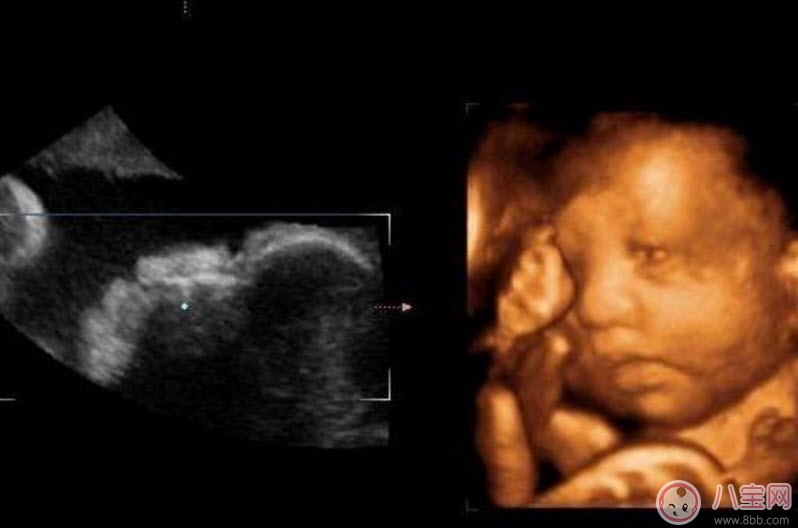

二維超聲可以理解為我們通常說的B超,顯示的是斷面圖像。何為斷面圖像?就是把西瓜切開,你在屏幕上只能看到西瓜的切面(斷面),但經(jīng)驗(yàn)豐富的你,可以只看這個(gè)切面(斷面)就知道這是一個(gè)西瓜。

三維、四維超聲就是把很多個(gè)二維斷面圖像通過計(jì)算機(jī)重建成一個(gè)立體的圖像。相當(dāng)于把切成很多片的西瓜,重新堆疊成一個(gè)完整的西瓜,這個(gè)堆疊過程由計(jì)算機(jī)完成。三維、四維的區(qū)別在于,三維是照片,四維是影片,四維就是會動的三維照片(實(shí)時(shí)三維)。